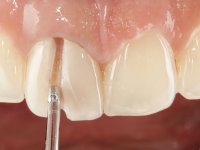

A pre-print was performed to make a crown in dual-cured resin. After a cross-section with a turbine, the infiltrated crown was removed with a microluxador. The dental stump was re-prepared to better define the shape and location of the cervical margin. It was necessary to place composite resin on the buccal surface of the provisional crown to improve its esthetics. The impression was made using a double-mix technique with two-viscosity, quick-setting silicones. In the laboratory, a crown with a ceramic-coated Zr infrastructure was made. After placing it in the mouth, we verified that the crown showed a greater translucency than the symmetrical one, not fulfilling our aesthetic goals. The ceramist had the opportunity to observe the situation in the clinic, collecting records for later rectification. The new crown was placed in the mouth and approved by the patient. The final cementation was done with resin-reinforced glass ionomer cement.